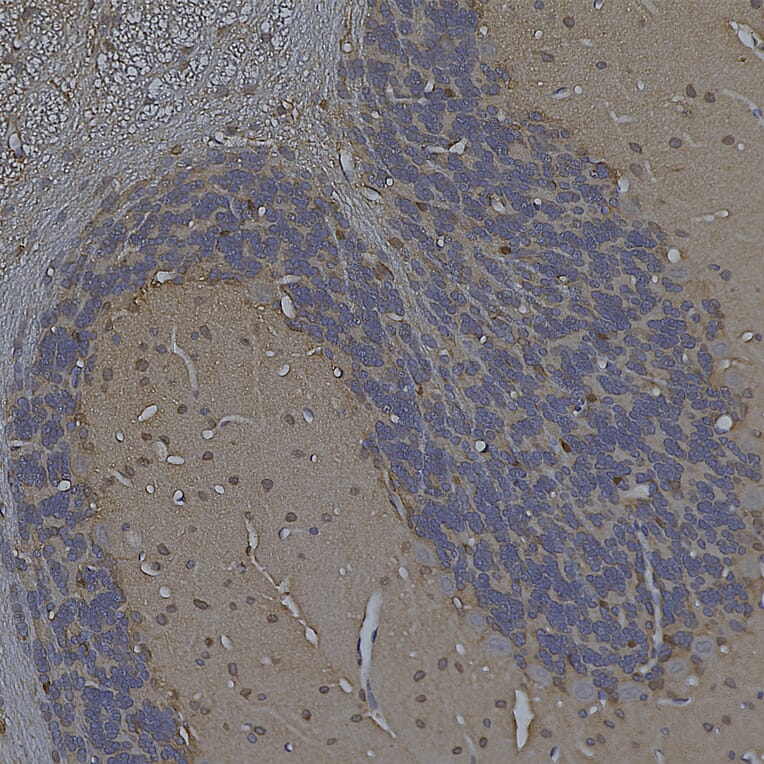

Immunohistochemistry analysis of a 4% PFA fixed paraffin embedded rat cerebellum section with Anti-Enolase 1 Antibody [253] (A85406) at a dilution of 1:1,000 detected with DAB (brown) using the Vector Labs ImmPRESS method and reagents with citra buffer retrieval. Counterstained with Hematoxylin (blue). The Anti-Enolase 1 Antibody [253] (A85406) labels the nuclei of non neuronal cells in the molecular and granular cell layers with a concentration at the nuclear membrane. Purkinje and granule neurons are notably negative. Note: this antibody performs well in testing with both 4% PFA and standard NBF fixed human and rat tissues.